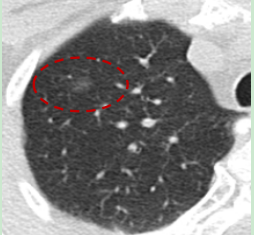

图四:百万像素 1024 * 1024 矩阵,有效提升微小病灶分辨能力

采用先进迭代重建算法与AI智能降噪技术,在低剂量下实现高清成像,显著提升早期肿瘤、血管斑块、细微骨折等微小病灶检出率,为临床诊断提供可靠支持。

高清精准,微小病灶可见